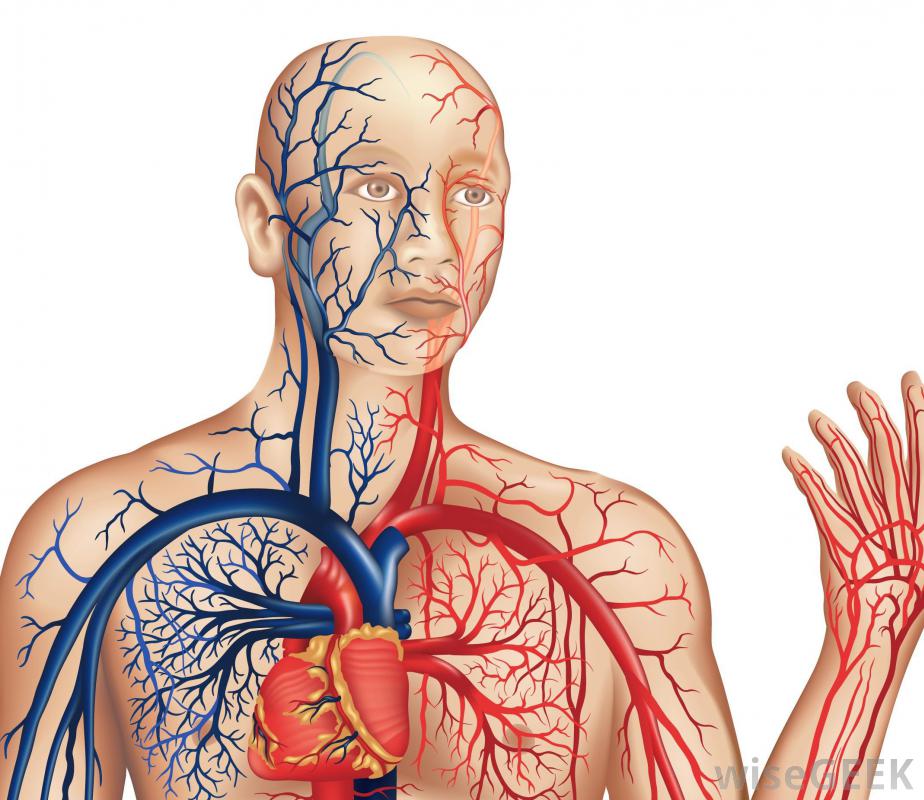

- Blood vessels (arteries, veins, and capillaries)